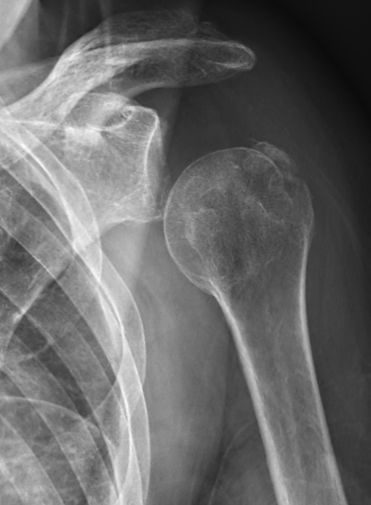

Röntgenbild där caput humeri ligger lågt i axelleden p.g.a. axillarispares. Här även fraktur i tuberkulum majus.